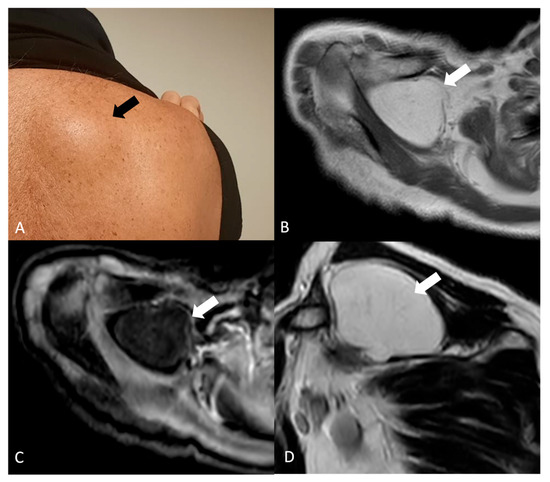

Lipomas (Figure 4) are benign tumors arising from adipose tissue and are the most common soft tissue tumors in adults and are generally more frequent in middle-aged and older adults, with a slight male predominance reported in some studies. Lipomas can manifest with a spectrum of clinical presentations depending on their size, location, and compression of adjacent structures (impingement syndrome, limited range of motion, and pain) [25].

Figure 4.

(A) Right shoulder bump of a 67-year-old male patient (black arrow). (B) Axial T1-weighted, (C) axial T1-weighted-fs and (D) sagittal T2w show a fat-containing (white arrow) lesion. No internal septations or nodular components are observed. The imaging features and typical superficial location are conclusive for a benign lipoma.

On US, lipomas appear as well-defined, hyperechoic lesions relative to surrounding muscle with a characteristic homogeneous internal structure. US may also be useful for guiding fine-needle aspiration biopsy for further evaluation [25]. On MRI, lipomas typically appear as well-circumscribed, high-signal intensity lesions on T1-weighted images with corresponding signal suppression on fat-suppressed sequences [25]. MRI can be particularly helpful in evaluating the extent of the lipoma and its relationship to surrounding neurovascular structures. On CT, lipomas appear as circumscribed, low-attenuation masses (typically approximately −65 to −120 HU) with minimal internal soft-tissue components. Areas of calcification may be present, although they are more frequently associated with well-differentiated liposarcoma [25].